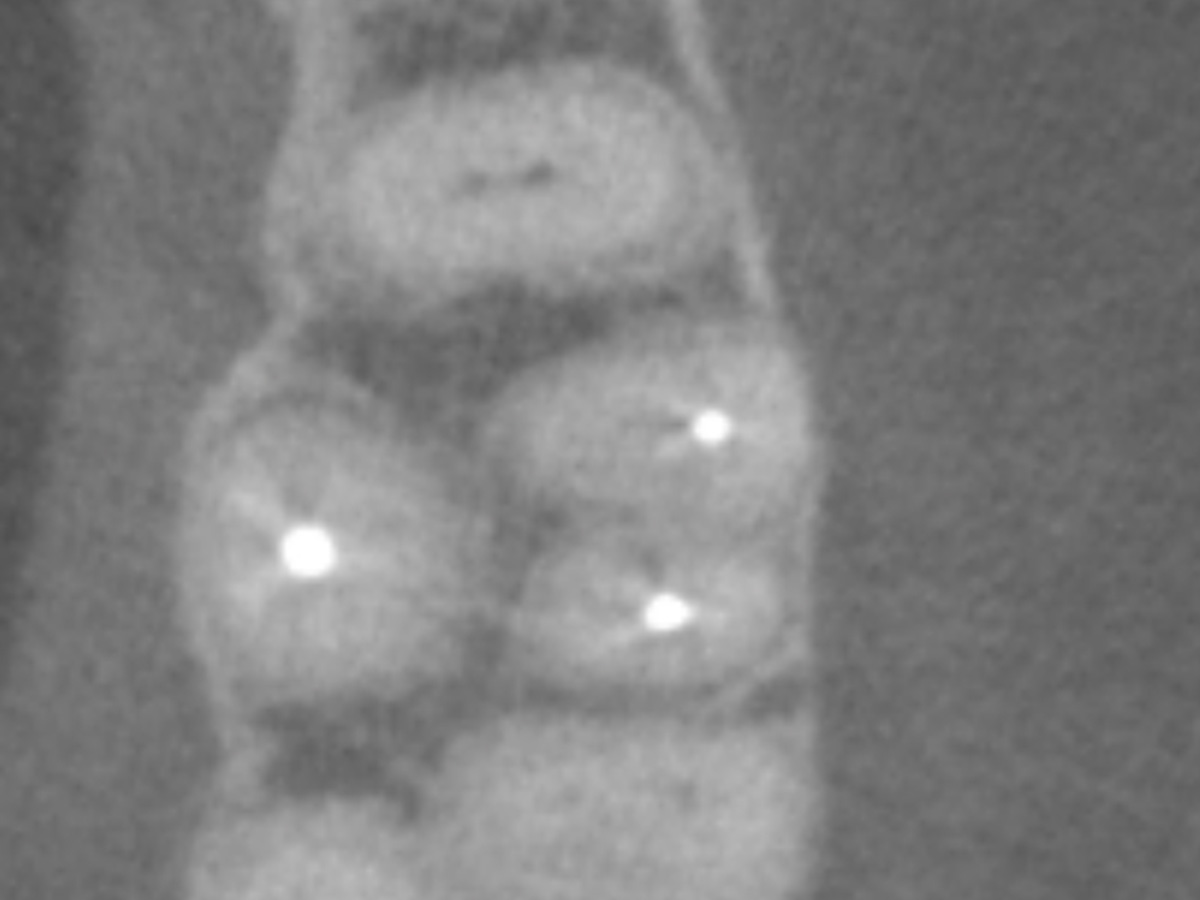

Der Patient stellte sich mit Aufbissschmerzen vor, wobei die klinische und röntgenologische Untersuchung eine symptomatische apikale Parodontitis an einem bereits wurzelkanalbehandelten Zahn 26 ergab. Die DVT-Aufnahme deutete auf einen unbehandelten zusätzlichen Kanal in der mesio-bukkalen Wurzel hin. Die Darstellung und Behandlung des mb2s sowie die Revision der bereits behandelten Kanäle erfolgte mit dem XP-endo® Rise Shaper bei einer hohen Umdrehungszahl von 2.500rpm.

DVT axial